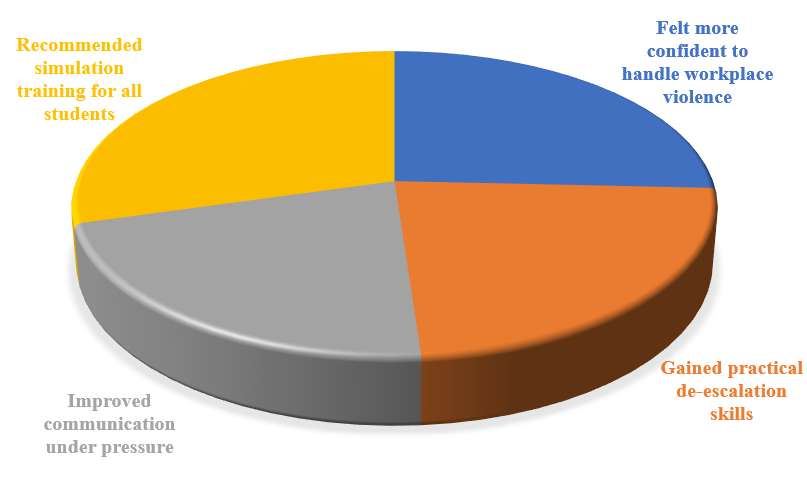

Perception and Effectiveness of Simulation-Based Training in Preparing Nursing Students to Handle Workplace Violence

Background: All over the world, workplace violence (WPV) among healthcare professionals, especially nurses, is increasing at an alarming rate. Because...Read More